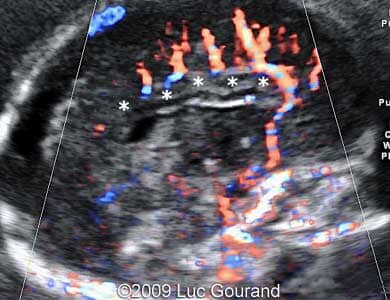

Images 5,6: Images show a Doppler imaging at 23 weeks.

Images 5,6: Doppler imaging of the mid-sagittal plane, the "pericallosal artery" has an unusual distribution, the wavy hypoechogenic structure in the position of the corpus callosum which is absent, is marked by *.

Case262_3

Case262_4